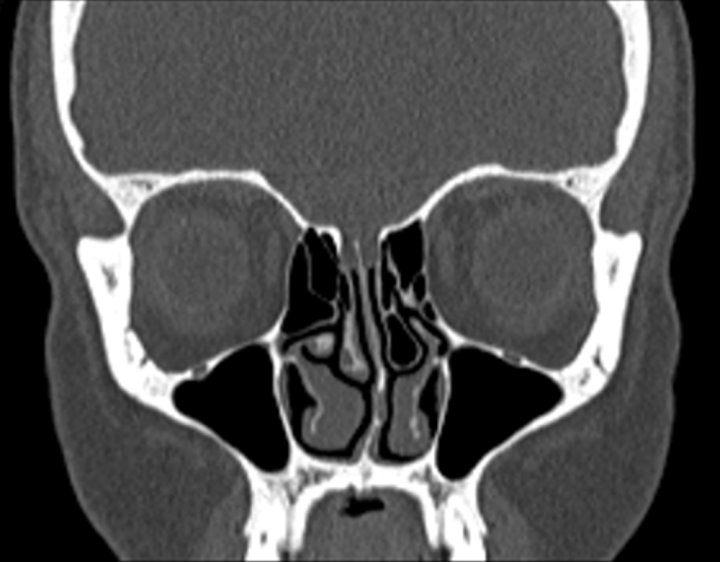

Click any image for labels.